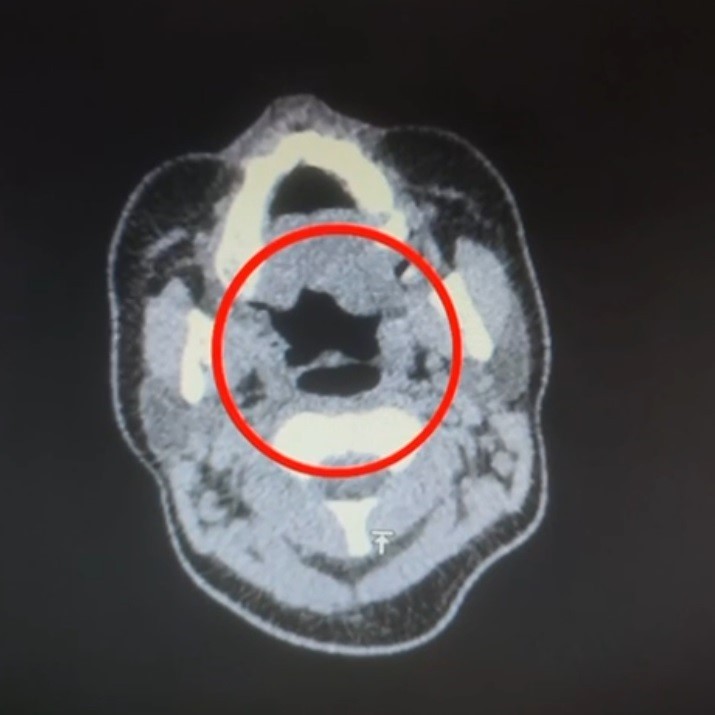

Şüpheli, hastaneye götürülerek iç beden muayenesine tabi tutuldu. Yapılan muayenede, şüphelinin midesinde 50 adet kapsül şeklinde toplamda 500 gram uyuşturucu madde bulunduğu tespit edildi.